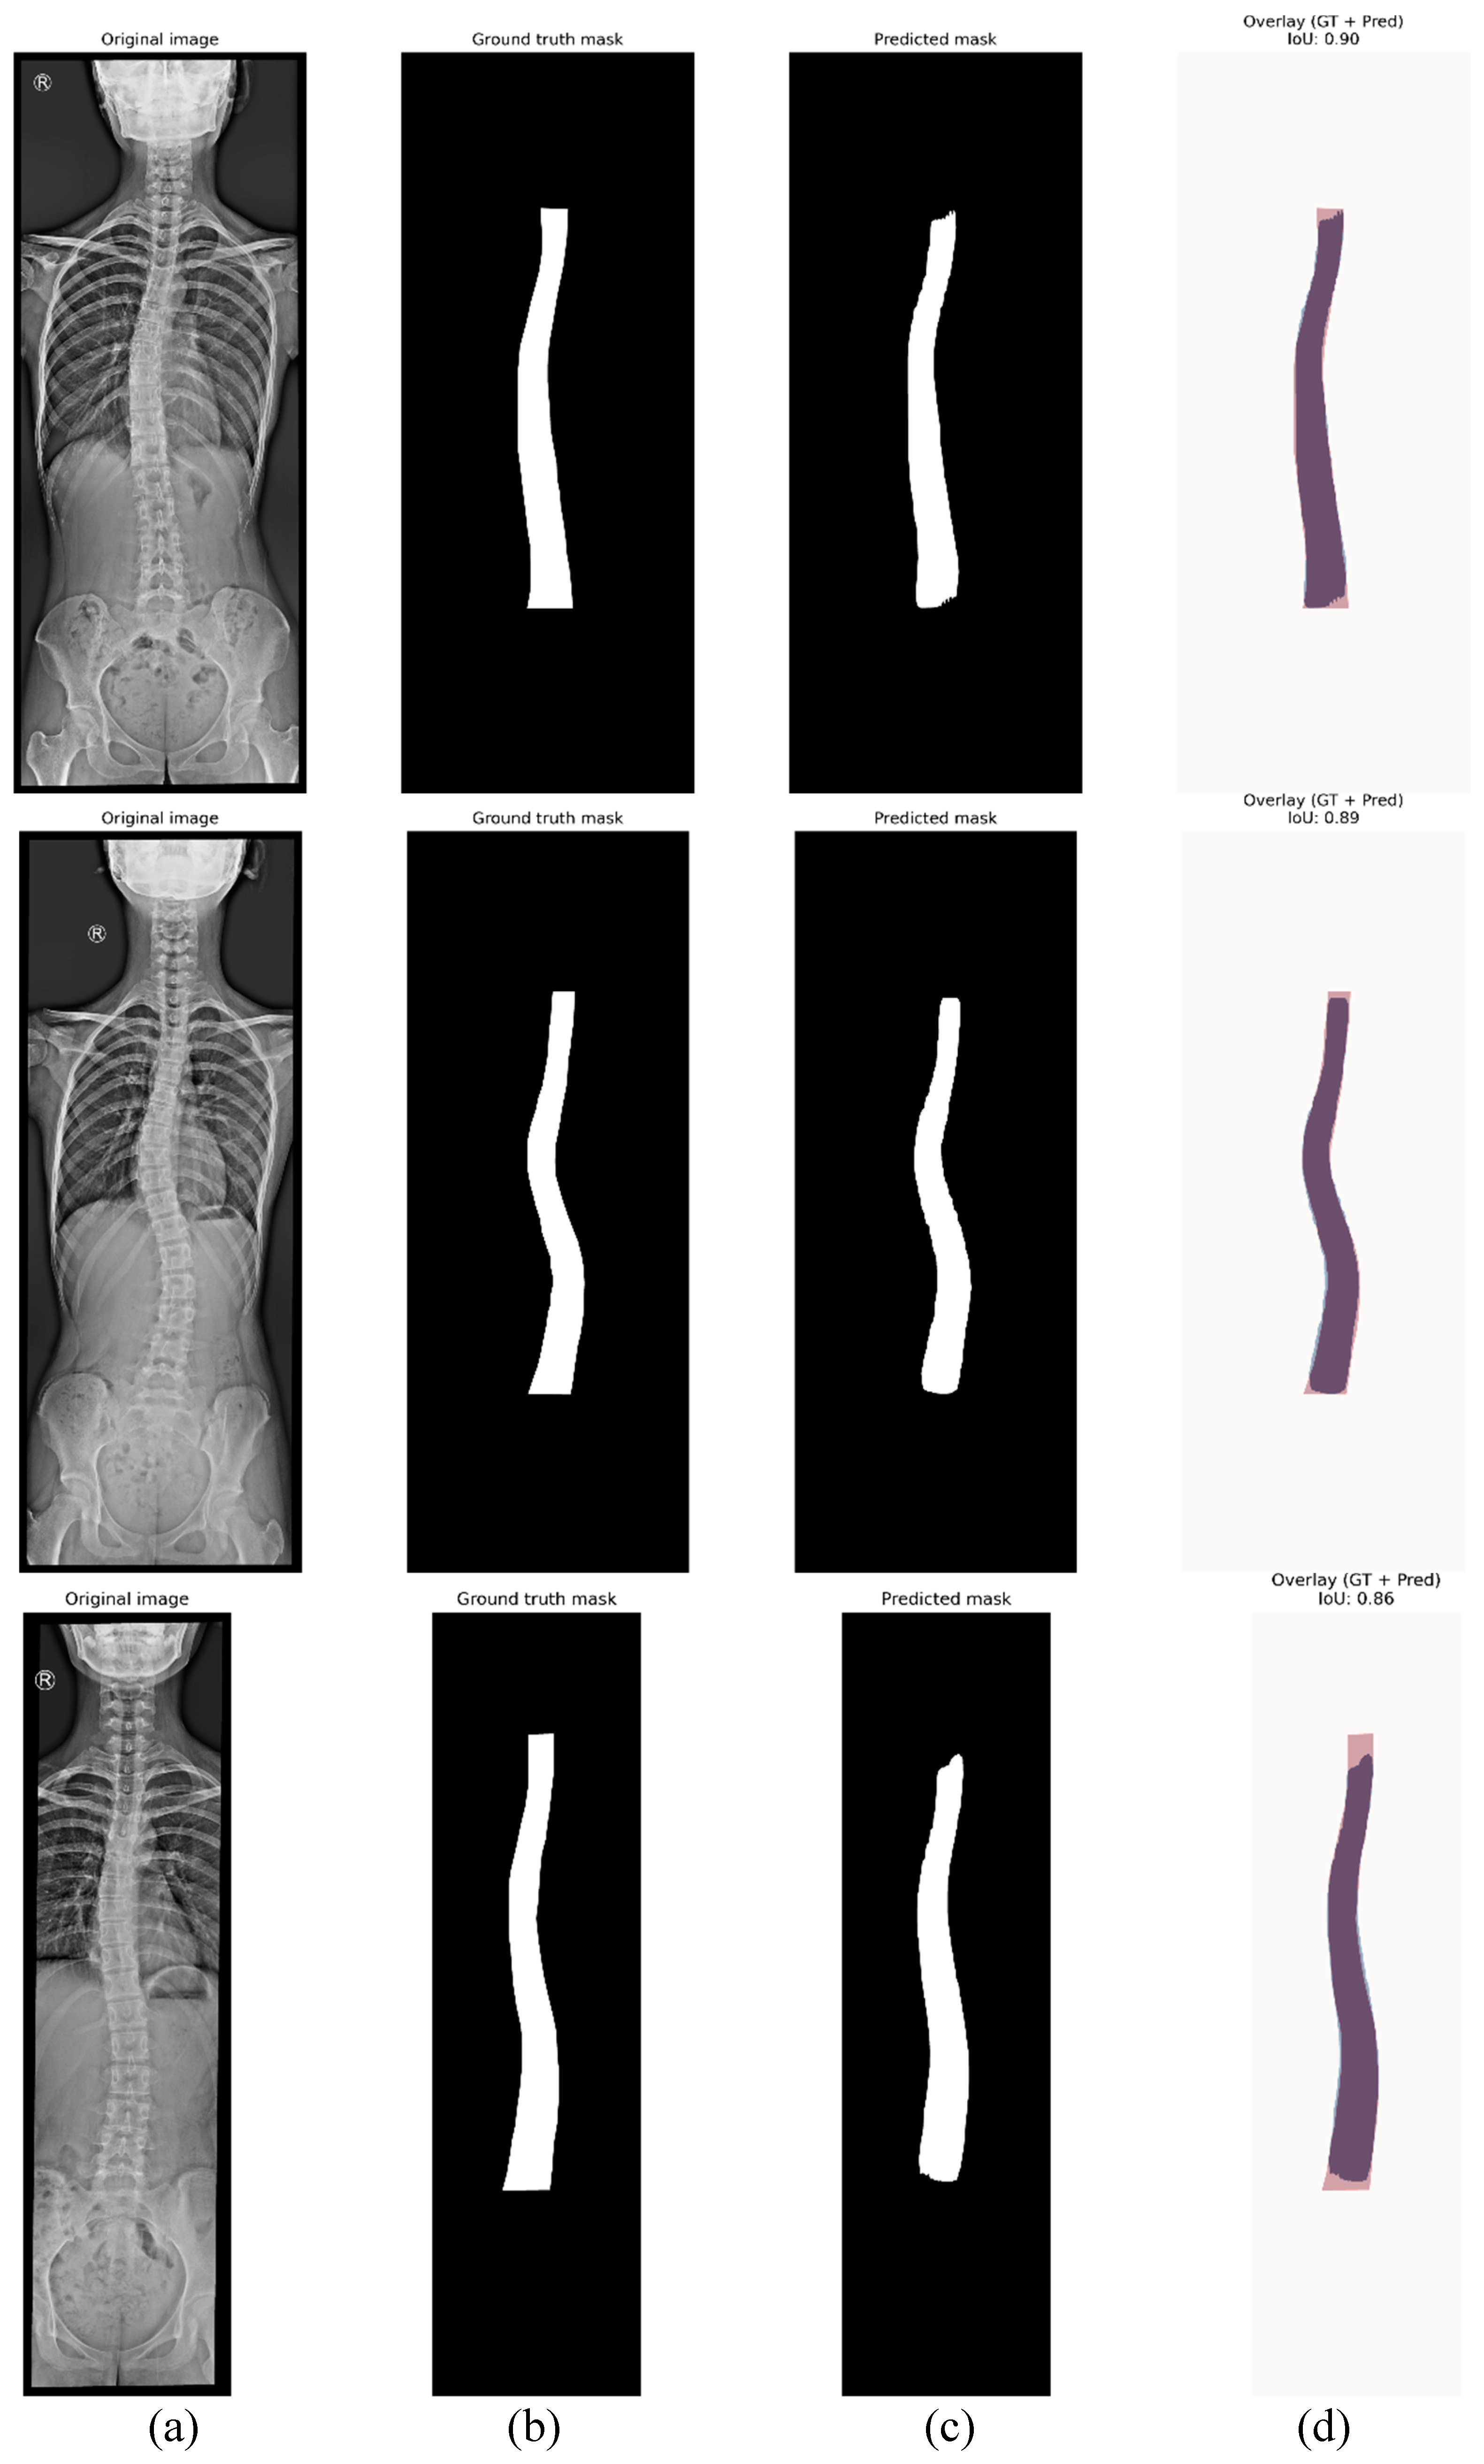

- Figure 6(b), shows the step corresponding with spinal segmentation using Mask R-CN. A pre-trained Mask R-CNN model is employed to perform instance segmentation of the spine. The model is loaded, and inference is conducted on the input image. To enhance segmentation reliability, only masks with a confidence score above a predefined threshold are retained. Among the detected regions, the mask with the largest segmented area is selected as the spinal region, assuming it corresponds to the spine. This approach ensures higher segmentation accuracy, reduces false positives, and improves spinal contour extraction. The accuracy of the proposed method in Cobb angle quantification and severity classification is highly dependent on the precision of generated mask. The more accurate the mask, the more precise the assessment.

4.1. Instance Segmentation